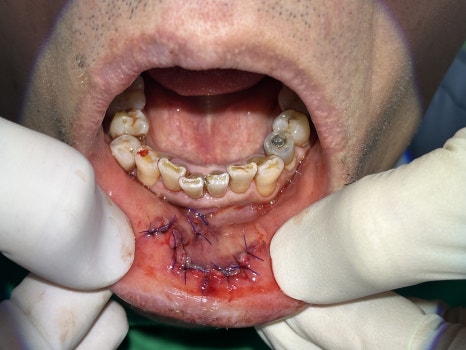

6 cm penetrating laceration on the outer lip, 4 cm on the inner lip

Multiple upper front teeth dislocated and loosened

Immediate tooth repositioning, followed by fixation with a resin-wire splint

🖼️ Lip trauma photo / Front tooth fracture and fixation photo / X-ray photo

Lip laceration immediately after the trauma / Initial emergency treatment photo showing fixation of the dislocated front tooth